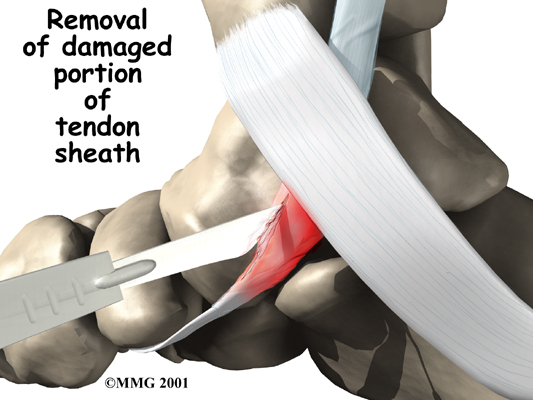

Tendon Debridement

If the problem appears to be primarily tendonitis with thickening of the tissue around the tendon (the tendon sheath), a tendon debridement operation can be performed to remove the thickened tissue around the tendon. This is done to try to decrease the symptoms of pain and to prevent rupture of the tendon.

This procedure is usually done through a small incision in the instep of the foot just over the posterior tibial tendon. The surgeon simply identifies the tendon and removes the thickened tissue.

Tendon Repair

A degenerated tendon that has not ruptured may only need to be repaired and not reattached. The surgeon divides the sheath around the tendon. Areas where the tendon is degenerated are carefully removed. Tears within the tendon are sutured along the length of the tendon. If the surgeon is concerned that the repaired tendon is at risk for rupturing, a graft procedure to add strength to the tendon may be needed (described below). The tendon sheath is repaired, and the skin is closed with sutures.